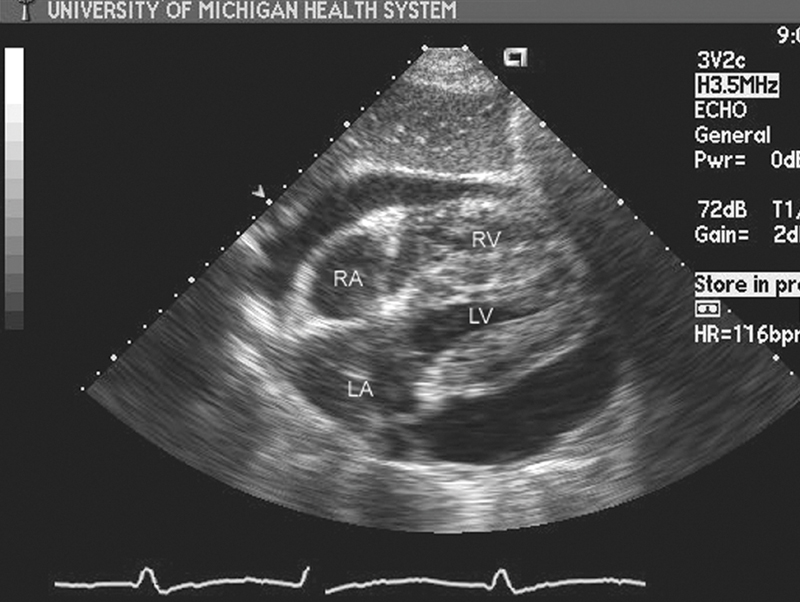

فحوصات تشخيصية لبعض امراض القلب والشرايين التاجية